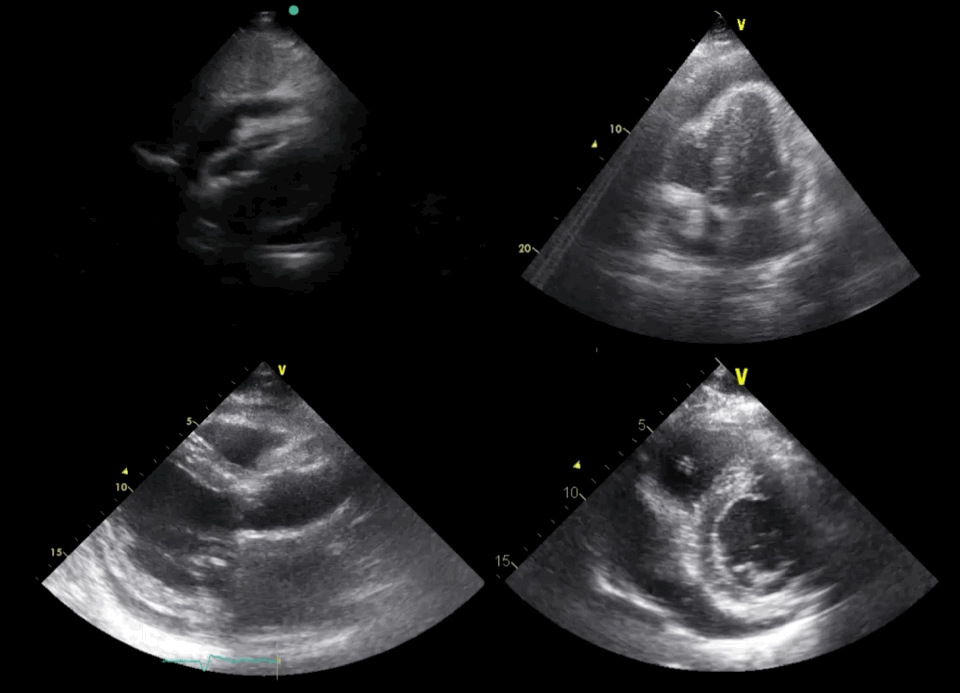

SC, A4CH, PLAX and PSAX views

All four standard cardiac views showing pericardial effusion: This clip presents all four standard cardiac views, each demonstrating pericardial effusion. The upper left shows the subcostal (SC) view, the upper right shows the apical 4-chamber (A4CH) view, the lower left shows the parasternal long-axis (PLAX) view, and the lower right shows the parasternal short-axis (PSAX) view. In all views, an anechoic (black) border is seen surrounding the heart, indicating the presence of a pericardial fluid collection.